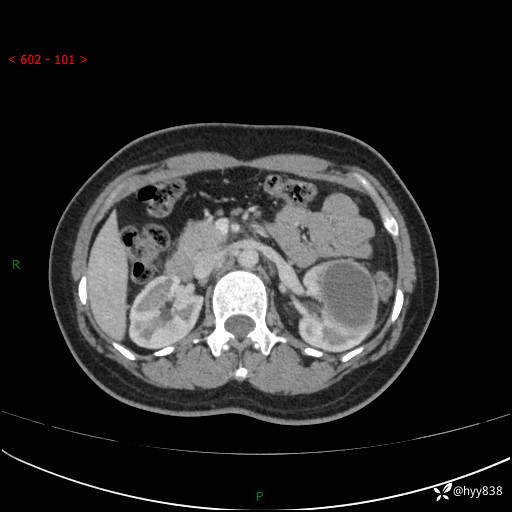

现病史:患者于1周前因左侧腰腹部间断胀痛不适,无恶心呕吐,无明显肉眼血尿,无畏寒发热,无尿频尿急,起病初,患者来我院就诊,查CT提示左肾低密度影,外周血提示:白细胞11.25*10^9/L.行抗感染治疗后未见明显好转,06-18泌尿系增强CT提示左肾类圆形低密度占位(脓肿?肿瘤?),大小:4.0*3.2cm,为求进一步治疗,门诊以“左肾占位”收住我科。 起病以来,患者精神佳,饮食、睡眠良好,大小便正常,体力体重无明显变化。

双肾CT平扫+增强